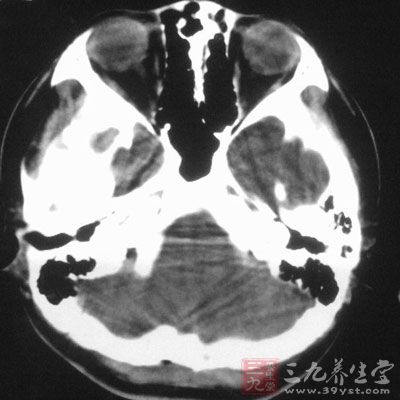

1、急性脑积水特征临床一般表现为头痛、恶心、呕吐、视力障碍等。2、慢性脑积水特征临床以慢性颅内压增高为

成人脑积水一般有什么表现 年长儿童及成人脑积水的临床特征 1、临床一般表现为头痛、恶心、呕吐、视力障碍